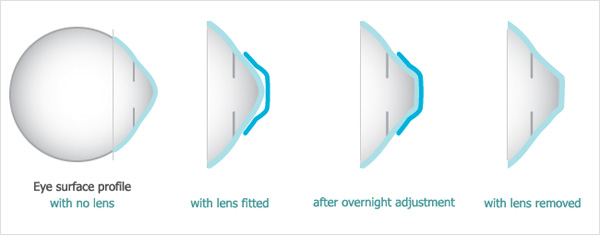

L'ortocheratologia è una tecnica non chirurgica e non invasiva per la riduzione reversibile della miopia, di alcuni casi di astigmatismo, di ipermetropia e di presbiopia, mediante lenti a contatto particolari, dette "a geometria inversa".

Già dopo la prima notte di utilizzo delle lenti potrai notare dei risultati evidenti. I tempi necessari per ottenere la correzione completa del difetto visivo, con risultati durevoli per tutta la giornata, variano da soggetto a soggetto, tenendo conto del grado di ametropia da correggere.